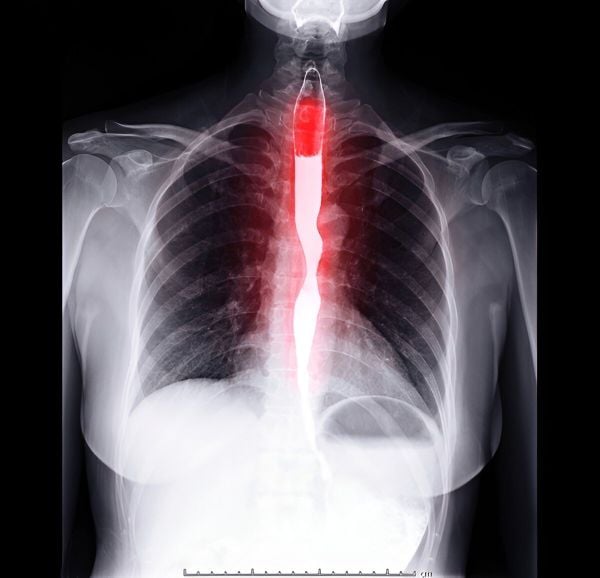

Hình ảnh chụp MRI của bệnh nhân bị đột quỵ - nhóm bệnh nhân dễ bị rối loạn nuốt nhất

Để xác định chính xác tình trạng rối loạn nuốt, bác sĩ sẽ tiến hành thăm khám lâm sàng, kiểm tra phản xạ nuốt, phản xạ ho và khả năng phối hợp thở – nuốt. Trong chẩn đoán hình ảnh, kỹ thuật chụp X-quang nuốt Bari (Barium Swallow) được xem là tiêu chuẩn vàng. Phương pháp này giúp bác sĩ quan sát toàn bộ quá trình di chuyển của thức ăn qua miệng, hầu, và thực quản, từ đó phát hiện vị trí tắc nghẽn hoặc rối loạn vận động. Trong một số trường hợp, bệnh nhân cần được nội soi hoặc chụp CT/MRI để tìm nguyên nhân cấu trúc hoặc tổn thương thần kinh liên quan.

Phương pháp Barium Swallow hoạt động bằng cách cho người bệnh nuốt dung dịch chứa bari để quan sát quá trình nuốt qua X-quang và phát hiện bất thường.